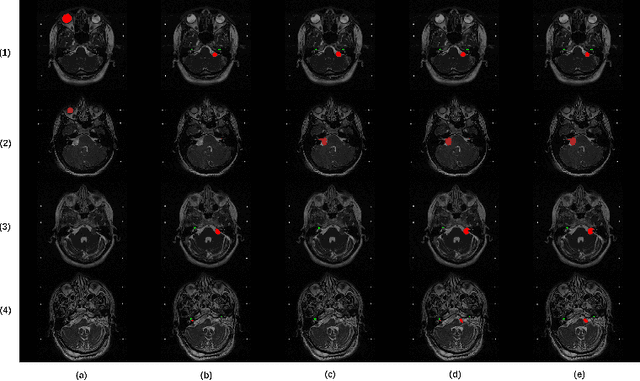

Abstract:The cross-Modality Domain Adaptation (crossMoDA) challenge series, initiated in 2021 in conjunction with the International Conference on Medical Image Computing and Computer Assisted Intervention (MICCAI), focuses on unsupervised cross-modality segmentation, learning from contrast-enhanced T1 (ceT1) and transferring to T2 MRI. The task is an extreme example of domain shift chosen to serve as a meaningful and illustrative benchmark. From a clinical application perspective, it aims to automate Vestibular Schwannoma (VS) and cochlea segmentation on T2 scans for more cost-effective VS management. Over time, the challenge objectives have evolved to enhance its clinical relevance. The challenge evolved from using single-institutional data and basic segmentation in 2021 to incorporating multi-institutional data and Koos grading in 2022, and by 2023, it included heterogeneous routine data and sub-segmentation of intra- and extra-meatal tumour components. In this work, we report the findings of the 2022 and 2023 editions and perform a retrospective analysis of the challenge progression over the years. The observations from the successive challenge contributions indicate that the number of outliers decreases with an expanding dataset. This is notable since the diversity of scanning protocols of the datasets concurrently increased. The winning approach of the 2023 edition reduced the number of outliers on the 2021 and 2022 testing data, demonstrating how increased data heterogeneity can enhance segmentation performance even on homogeneous data. However, the cochlea Dice score declined in 2023, likely due to the added complexity from tumour sub-annotations affecting overall segmentation performance. While progress is still needed for clinically acceptable VS segmentation, the plateauing performance suggests that a more challenging cross-modal task may better serve future benchmarking.

Abstract:Domain Adaptation (DA) has recently raised strong interests in the medical imaging community. While a large variety of DA techniques has been proposed for image segmentation, most of these techniques have been validated either on private datasets or on small publicly available datasets. Moreover, these datasets mostly addressed single-class problems. To tackle these limitations, the Cross-Modality Domain Adaptation (crossMoDA) challenge was organised in conjunction with the 24th International Conference on Medical Image Computing and Computer Assisted Intervention (MICCAI 2021). CrossMoDA is the first large and multi-class benchmark for unsupervised cross-modality DA. The challenge's goal is to segment two key brain structures involved in the follow-up and treatment planning of vestibular schwannoma (VS): the VS and the cochleas. Currently, the diagnosis and surveillance in patients with VS are performed using contrast-enhanced T1 (ceT1) MRI. However, there is growing interest in using non-contrast sequences such as high-resolution T2 (hrT2) MRI. Therefore, we created an unsupervised cross-modality segmentation benchmark. The training set provides annotated ceT1 (N=105) and unpaired non-annotated hrT2 (N=105). The aim was to automatically perform unilateral VS and bilateral cochlea segmentation on hrT2 as provided in the testing set (N=137). A total of 16 teams submitted their algorithm for the evaluation phase. The level of performance reached by the top-performing teams is strikingly high (best median Dice - VS:88.4%; Cochleas:85.7%) and close to full supervision (median Dice - VS:92.5%; Cochleas:87.7%). All top-performing methods made use of an image-to-image translation approach to transform the source-domain images into pseudo-target-domain images. A segmentation network was then trained using these generated images and the manual annotations provided for the source image.